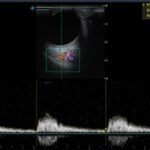

Imágenes C y D: las arterias ciliares, central de la retina flujos anterógrados normales, con espectrometría en parámetros normales (no hay alteración vascular).